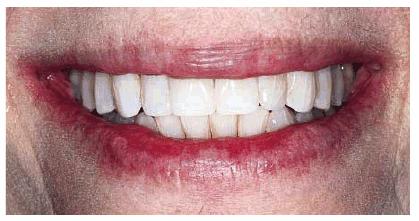

Goldstein cited the revolutionary concept that esthetic dentistry is, in fact, a health service.6 During the last decade, older adults who elected to have treatments that involved all esthetic disciplines embraced this concept of oral health. A good example of an older adult undergoing extensive esthetic dental treatment appears in Figures 29-1A to C 29-1D to F 29-1G 29-1H 29-1I and J 29-1K 29-1L 29-1M 29-1N, and 29-1O

Figure 29-1A to C: This 76-year-old lady presented for treatment after a lifetime of dissatisfaction with her crowded teeth.

Figure 29-1G: After the removal of the orthodontic appliances, the teeth are much straighter but still discolored.

Figure 29-1H: After restorative treatment featuring tooth- colored restorations and bleaching, the patient has the smile she has always wanted.

Figure 29-1I and J: Note that the formally eroded cervical areas have better contour and will deflect food particles better.